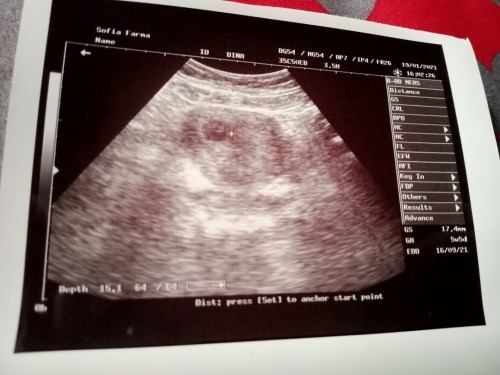

Bun, aku usg bru 5w tapi janin nya msh blum kelihatan & kantong janin nya msh di atas, normal kh bun

Soalnya sblumnya pernah kuret

msh normal kok. sy jg USG TV 5w msh berupa kantung ukuran 0,5cm. selama letaknya d dlm rahim masih aman, bisa kontrol ulang sesuai dgn rekomendasi dokternya